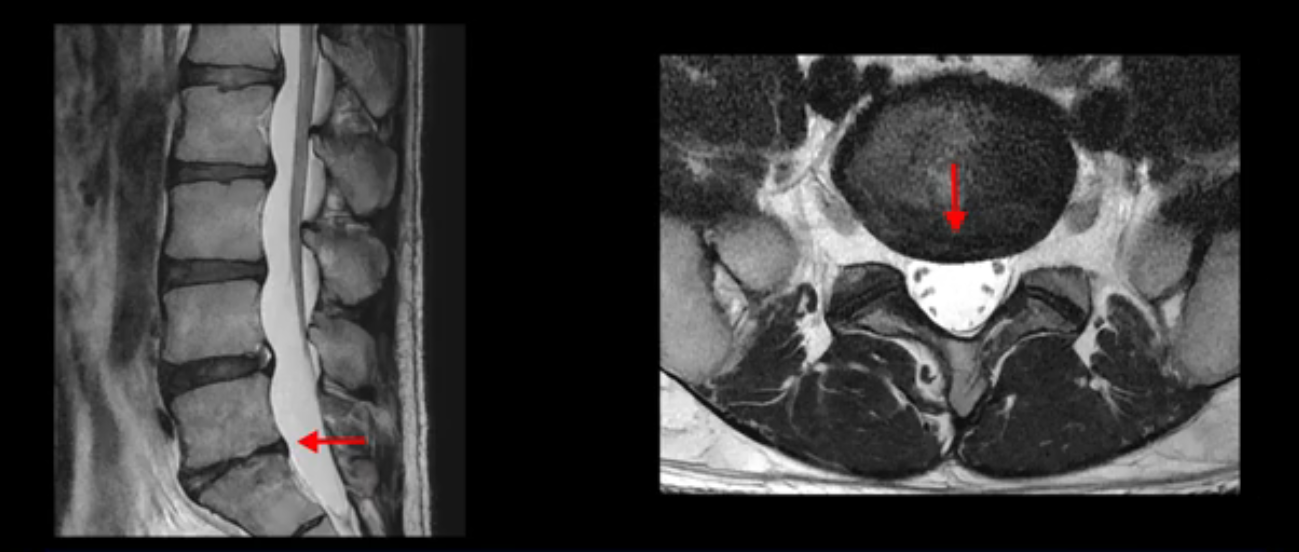

앞서 1번 2번, 4번 5번, 5번 1번의 디스크가 찢어지고 조금 밀려 나온 게 최근에 찢어진 게 아니고 오래된 걸로 보인다고 말씀 드렸죠. 왜 그럴까요? 만약 급성으로 찢어진 것이라면 아주 심한 디스크성 통증이 있겠죠. 기침이나 재채기를 하면 심하게 아프고 허리를 조금만 구부리거나 비틀면 아주 날카로운 통증들이 생길 겁니다. 그런데 이분은 이런 증상이 전혀 아닙니다. 또 디스크의 밀려나온 정도도 전혀 심하지 않기 때문에 이분이 가지고 계신 양쪽 다리 저림, 특히 이분은 누워있을 때도 양쪽 발이 발가락까지 쑤신다고 하는데 이정도 디스크 때문에 그런 증상은 생길 수가 없는 겁니다. 이처럼 이분의 가벼운 디스크 탈출은 이미 오래 전에 진행되었고 섬유륜 자체는 이미 아문 상태인데도 디스크내장증을 진단받은 환자들 중에는 본인이 섬유륜 파열 환자라고 끝까지 믿는 분들이 많습니다. 다시 말하지만 디스크내장증이라는 진단을 받은 환자들을 보면 거의 전부 다 섬유륜 파열 증상이 아닙니다. 증상이 완전히 다릅니다. 진단이 애초에 잘못되면 어떤 치료를 받아도 좋아질 수 없습니다.

이분은 어떤 한 병원에서 디스크 내장증 얘기를 들으셨는데요. 여기 보시는 것처럼 4번 5번의 하얀 HIZ(High Intensity Zone)을 보고 디스크 내장증의 근거로 얘기하는 병원들이 있는데,

이 HIZ는 섬유륜이 찢어졌다가 이미 아문 뒤에도 얼마든지 보일 수 있는 흔적일 가능성이 있어서 재채기를 하면 아픈지, 허리를 구부릴 때 날카로운 통증이 생기는가 등의 증상으로 구별해야 하는데 MRI만 보고 HIZ가 보이면 그게 마치 통증의 원인인 것처럼 얘기하는 의사들이 있습니다. 이분 MRI를 자세히 보고 증상을 정말 자세히 들어본 의사가 있었더라면 다른 환자분들처럼 증상과 MRI가 일치하지 않는다는 얘기를 들을 수 있었을 텐데 이분은 그런 얘기는 듣지 못했습니다.